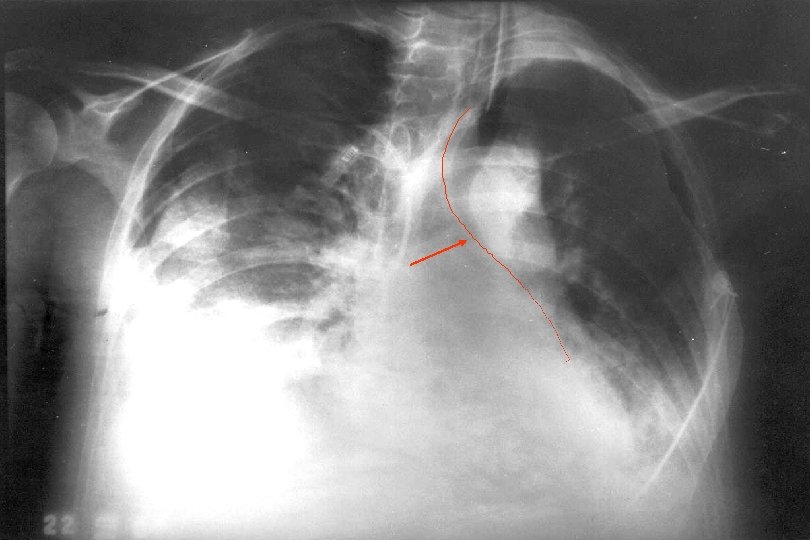

Raio X Padrão ouro posicionamento da sonda 86% enfermeiras utilizam apenas método auscultatório Wentzel, 2006 (Crit Care Nurs)

Mau posicionamento da sonda Trato respiratório Esôfago SNC Metheny, 2007 (Curr Opin Gastroenterol)

Confirmar com raio X

Cuidados nutrição enteral Raio x após passagem da sonda Utilizar sondas flexíveis Utilizar sonda por 4 semanas Lavar sonda com 20 a 30 ml H 2 O Elevação cabeceira da cama 30º Administração por infusão contínua Cuidados com hiperglicemia e realimentação